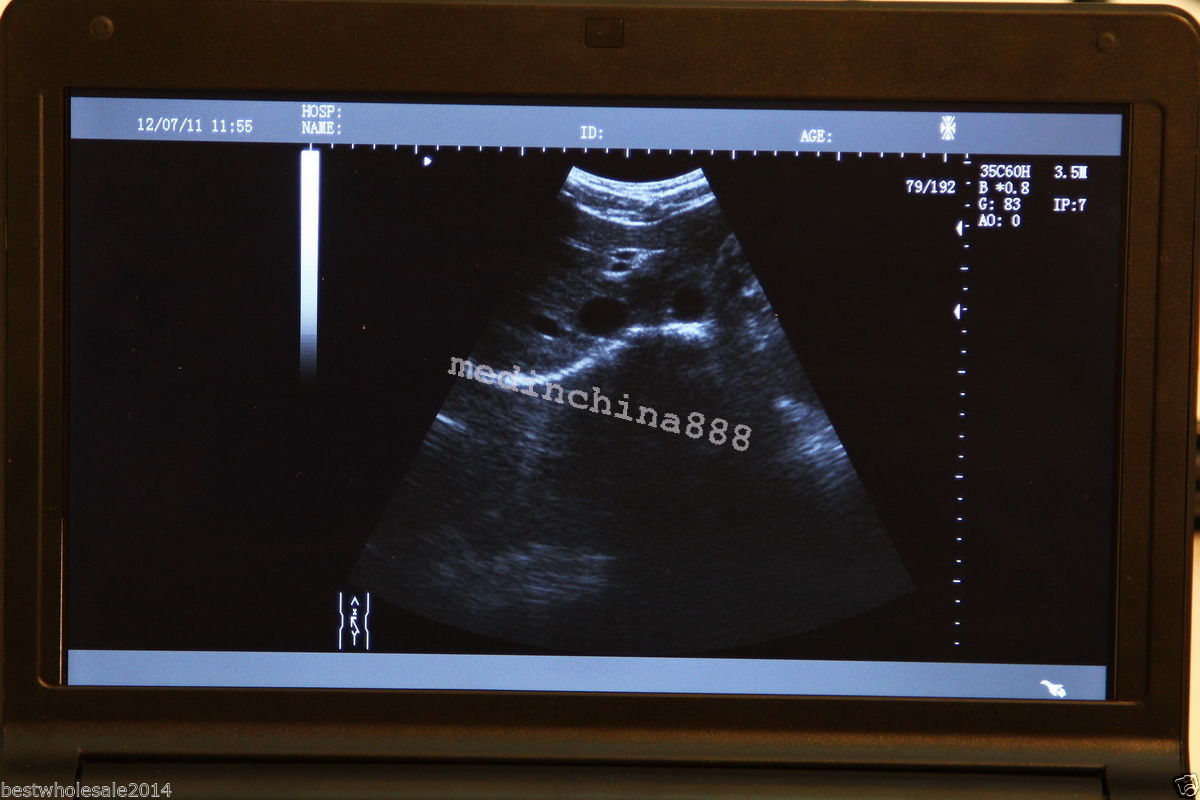

monitor: 10.1â high-resolution TFT LCD

The Laptop LCD Digital 10.1-Inch Ultrasound Scanner is designed for high-quality imaging. This portable device offers detailed visuals, allowing healthcare professionals to deliver accurate diagnoses effortlessly. Equipped with both convex and transvaginal probes, it enhances versatility in various medical procedures. Its compact design ensures that you can carry it easily between locations, making it an essential tool for any medical practice. The user-friendly interface further simplifies operation, so you can focus on patient care without unnecessary distractions.

This ultrasound scanner is not only portable but also built for convenience. The 10.1-inch LCD screen displays clear images, which means you can view results in real-time without any lag. It provides essential features like freeze and rewind functions, enabling you to review images quickly. Additionally, because it connects easily to printers or USB devices, you can generate hard copies of your findings without any hassle. So, whether in a clinic or at a patient's home, this laptop ultrasound scanner adapts to your needs.